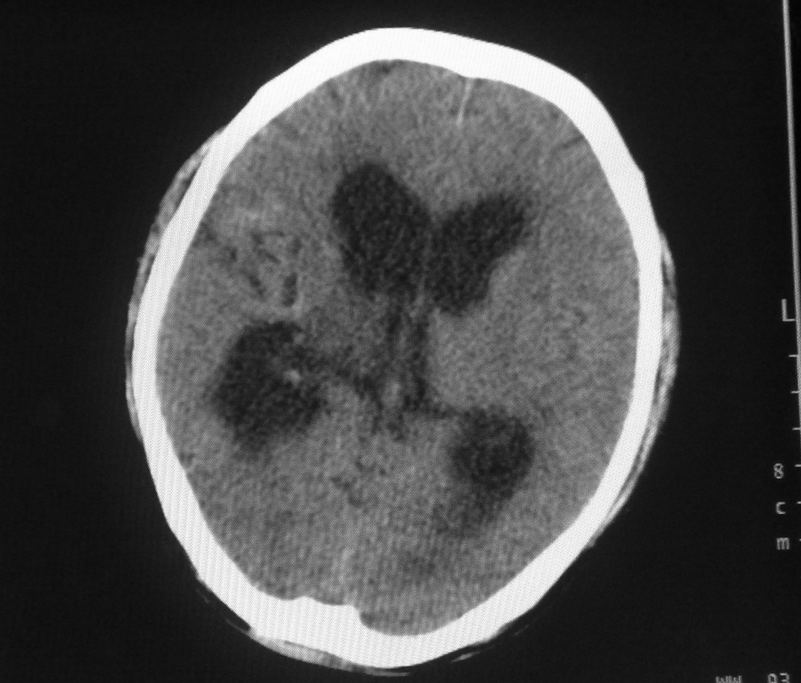

标题: CT24862:男,61岁,发热,有脑出血病史。 [打印本页]

男,61岁,发热,有脑出血病史。

脑积水【脑室血块阻塞?】

脑积水!四脑室显示不清,导水管梗阻?建议mri!

右侧基底节及放射冠软化灶,脑积水,四脑室显示不清,导水管梗阻?建议mri!

梗阻性脑积水,出血后粘连所致

1)右侧基底节区、右侧放射冠及右侧丘脑软化灶。2)脑积水。